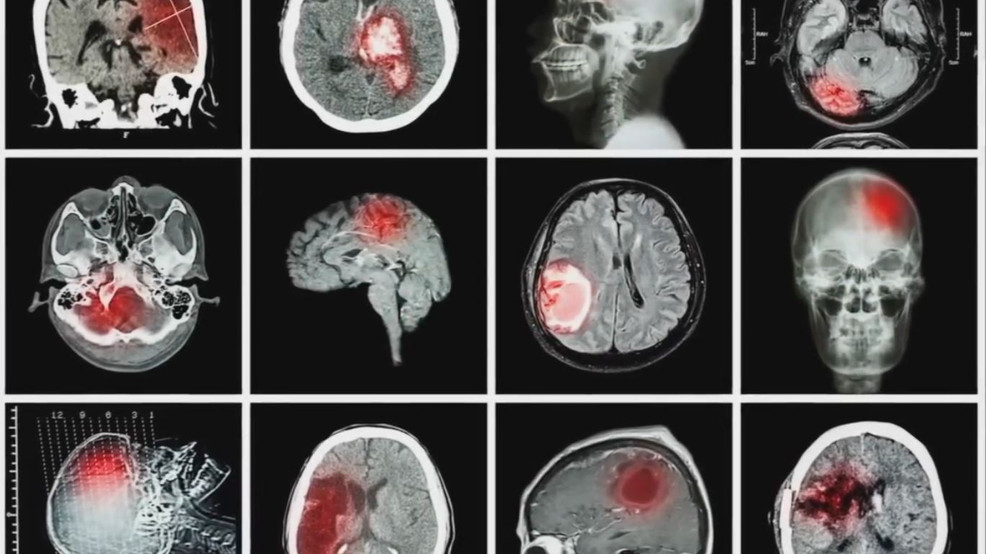

“No pude responder. No tenía ni idea. Fue entonces cuando pensamos que estaba teniendo un derrame cerebral”, cuenta Rebecca. Cuando la ambulancia la trasladaba, solo pensaba que llegaría al hospital a morir.